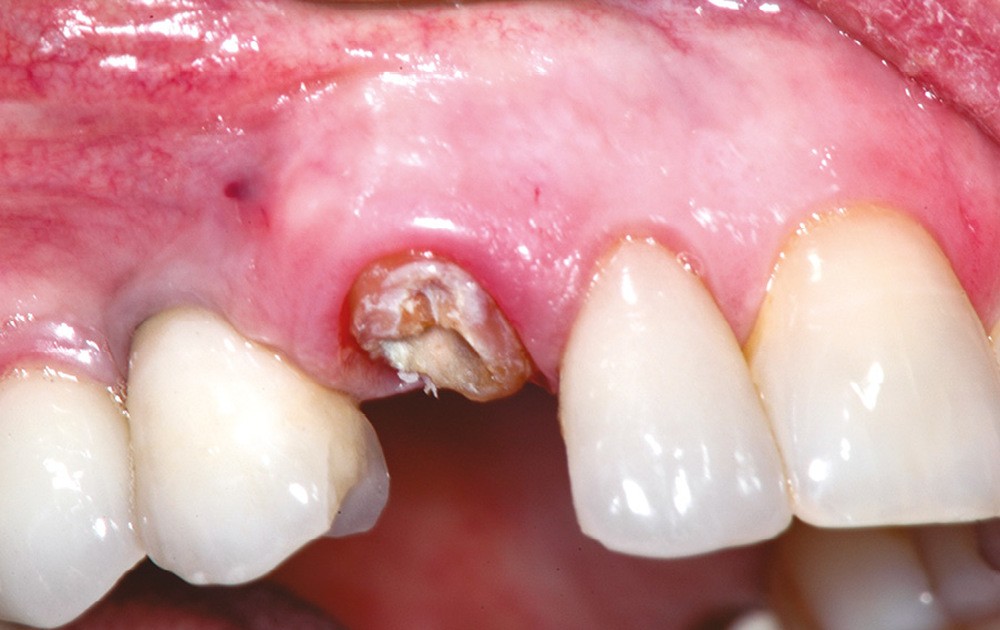

4. Canine supérieure droite fracturée.